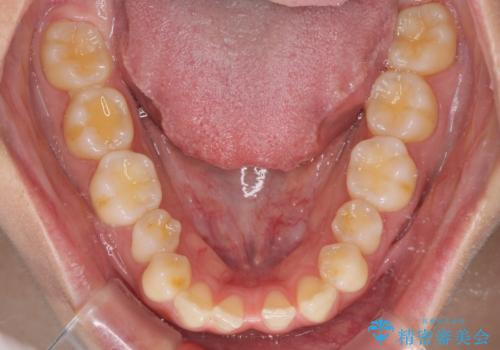

下顎前歯が2歯欠損しており、スペースになっており、上顎は叢生歯列となってしました。

奥歯の咬み合わせを考えると、理想的には2歯、最低でも1歯は下顎前歯の欠損部にインプラントやブリッジにより歯数を増やす必要がありました。

周囲の歯を削らないようにするためインプラントがおすすめとなりますが、歯根の移動が不十分な場合にはインプラントを埋入する幅が獲得できないため、その場合にはオールセラミックブリッジにより補綴治療を行うこととして、矯正治療を行うこととしました。

当初は上記計画でしたが、レントゲン撮影よりインプラント埋入は困難と判断され、患者様と相談の上、歯を削ってブリッジとするよりも、奥歯の咬み合わせを多少妥協することとなっても、スペースを閉じて仕上げていくこととしました。